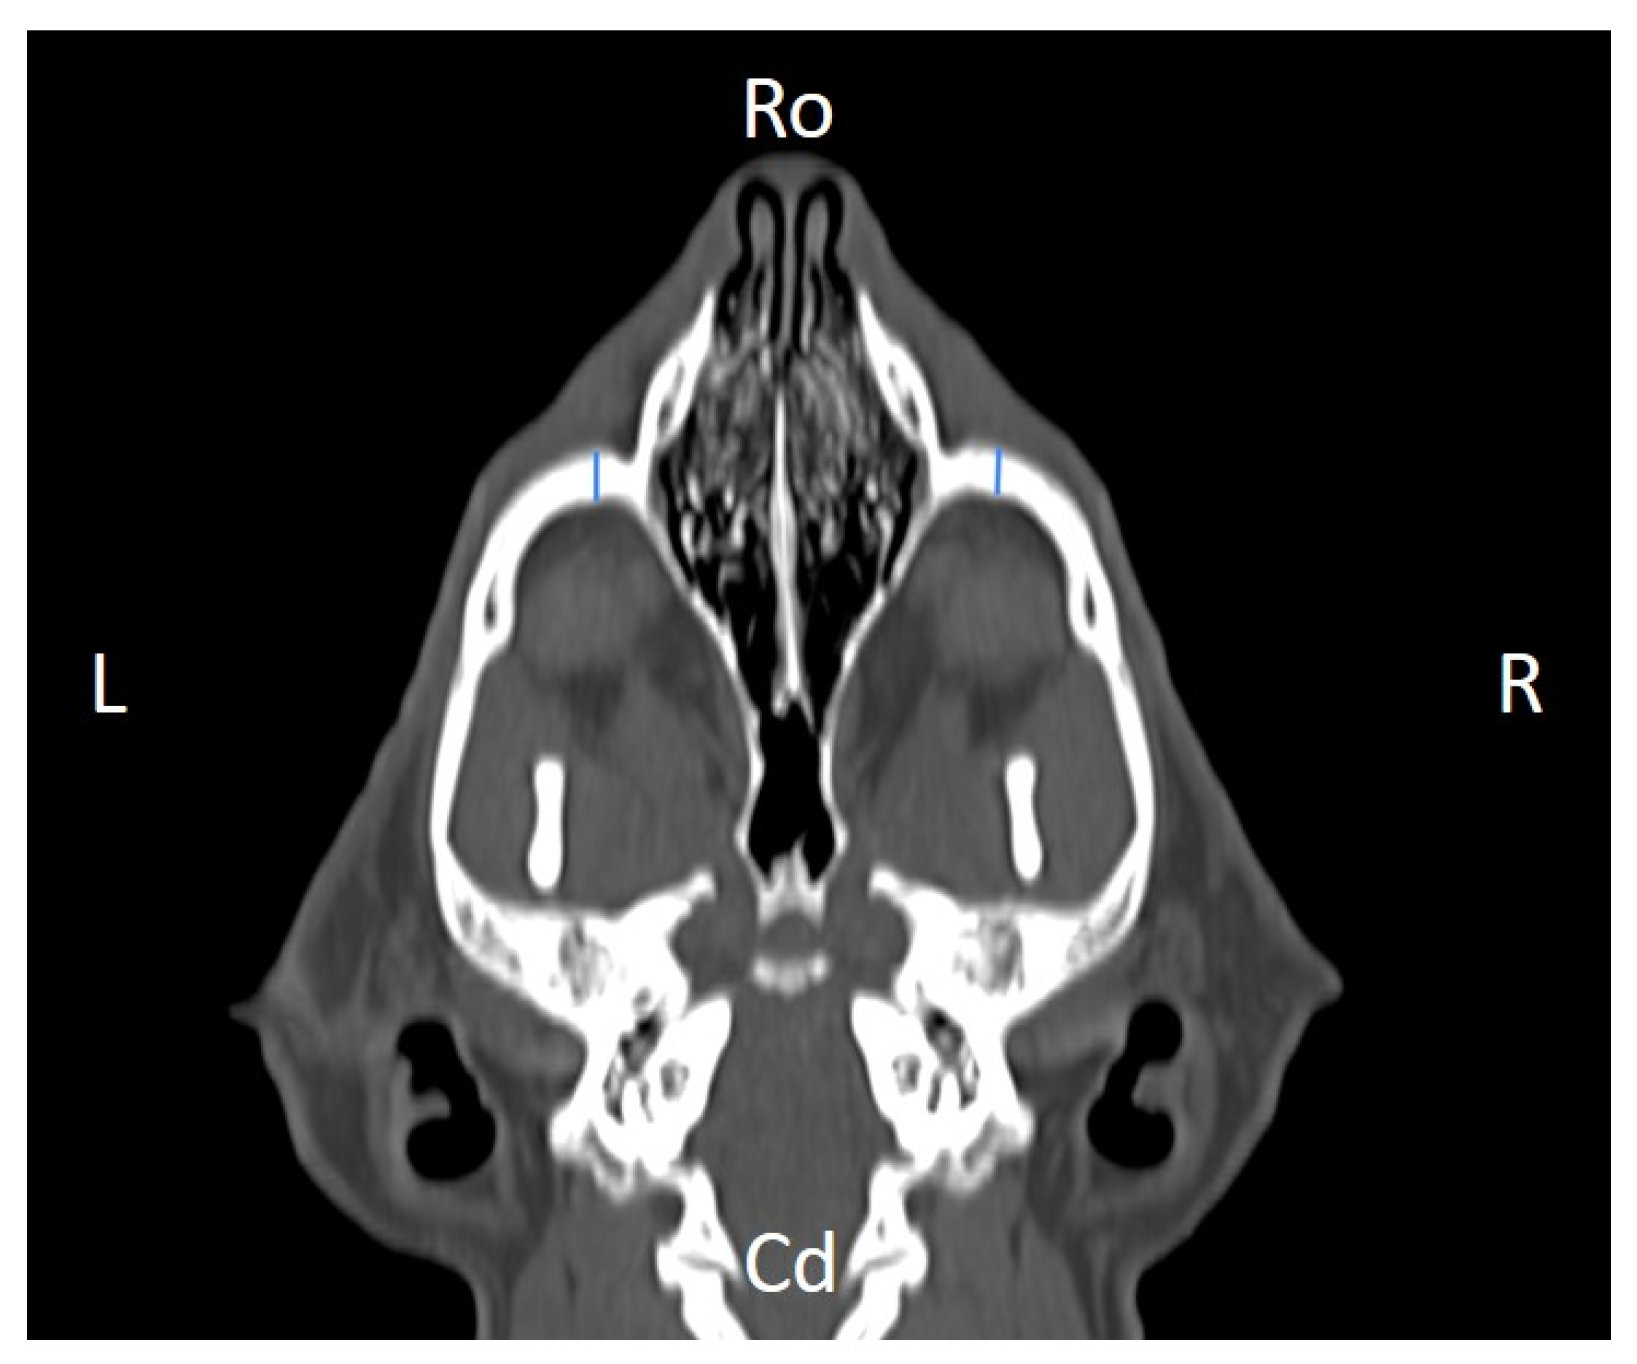

Figure 4. Infraorbital canal length (ICL) measured at the left and right sides, on a dorsal CT image (blue lines). Cd, caudal, L, left, R, right, Ro, rostral.